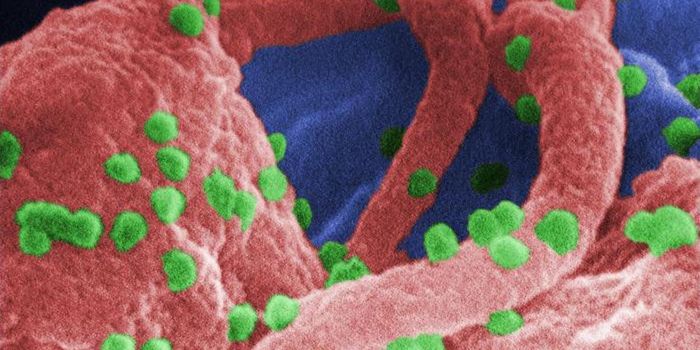

SEP 20, 2021Genetics & GenomicsHuman immunodeficiency virus (HIV) is a retrovirus, which is a type of virus that can write its genetic material into th ...